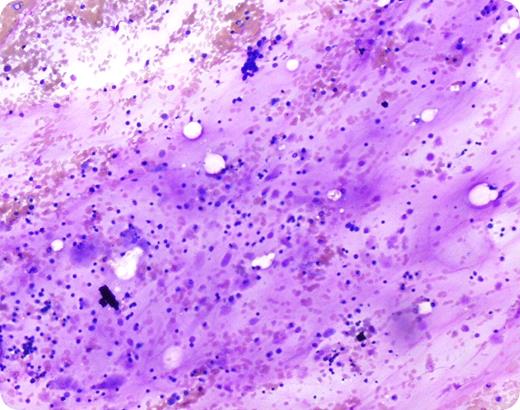

A 25-year-old white female with a history of an eating disorder presented with pancytopenia. Hematopoietic elements including erythroid precursors and megakaryocytes can be recognized in addition to a few fat cells. The amorphous material represents deposit of hyaluronic acid with gelatinous transformation of the marrow. (Wright-Giemsa stain, 10× magnification)

The above image was first published in the ASH IMAGE BANK, a reference and teaching tool that is continually updated with new atlas images and images of case studies. For more information or to contribute to the Image Bank, visit www.ashimagebank.org.